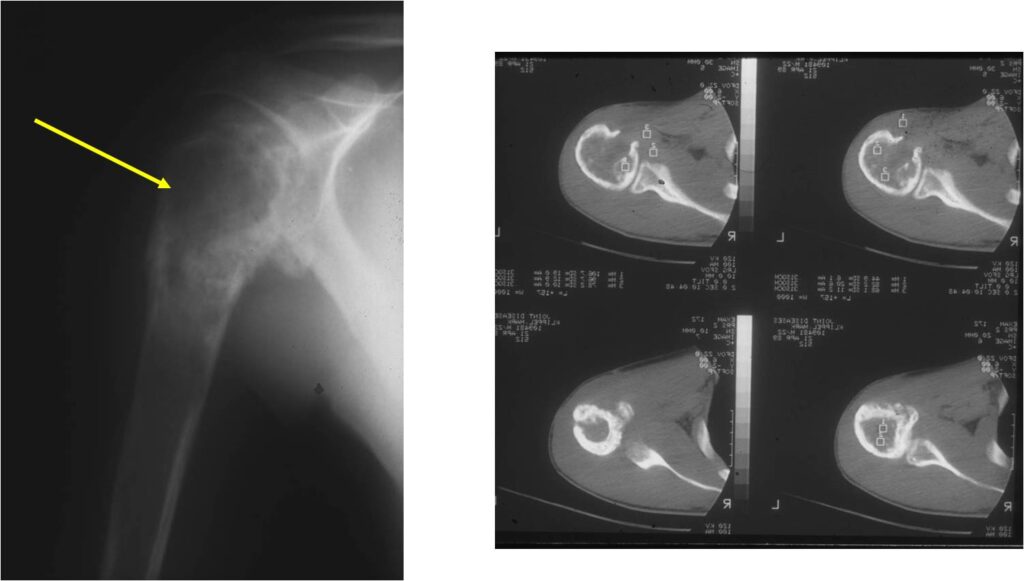

Radiographic Presentation

- Permeative or moth eaten bone destruction

- Ill defined and malignant appearing

- Bony changes are often subtle

- Soft Tissue Mass in 90% of of cases

- Periosteal Reaction in 50% of cases

- Onion Skin (colic pattern of irritation)

- Hair on End (rapid continuous lifting of periosteum)

- Reactive Bone Sclerosis is rare but occurs in 10% of cases

- No cartilage or bone production by tumor

- Pathologic fracture in 10-15%